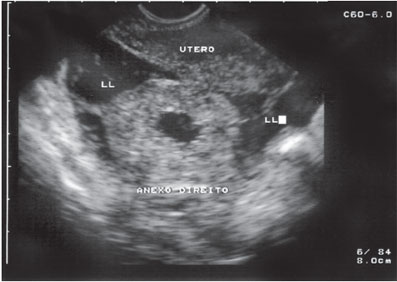

Figura 37.1: Gravidez ectópica rota. (LL, líquido livre.)